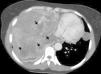

En las exploraciones de imagen, la radiografía de tórax (fig. 1A y B, flechas) mostró una opacidad homogénea del lado derecho que afectaba a la mayor parte del pulmón derecho, con derrame pleural, desviación de la tráquea a la izquierda y 2 opacidades redondeadas en forma de moneda en el campo pulmonar izquierdo (flechas). En una exploración adicional, la tomografía computarizada (TC) de tórax (fig. 2) reveló la presencia de una masa heterogénea grande con múltiples focos de necrosis (puntas de flecha) y un colapso del pulmón derecho. Las dos lesiones en forma de moneda observadas en la radiografía de tórax en el pulmón izquierdo fueron confirmadas por la TC. El mediastino estaba desviado a la izquierda, sin ninguna adenopatía significativa.